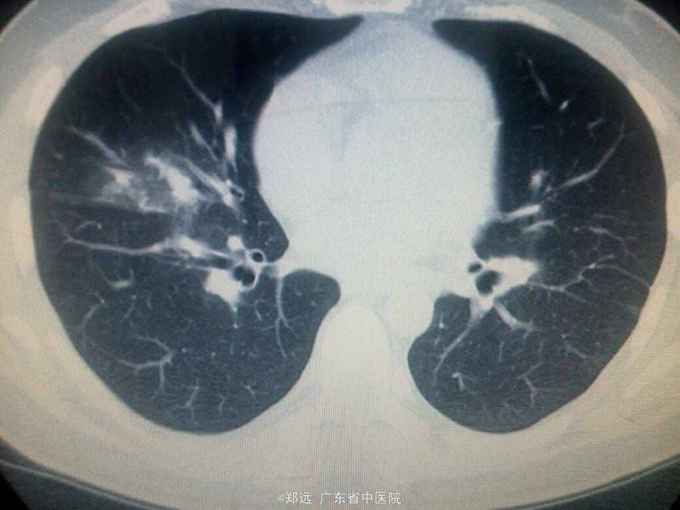

体查:双下肺湿啰音。三尖瓣区3/6级收缩期杂音。 胸部ct:双肺斑片结节影并空洞形成,左胸少量积液。血色素88克/升,白细胞11.48,中性粒81.3%,降钙素原14.84,ALT 121,AST 134.超声提示三尖瓣赘生物,三尖瓣大量返流。血培养金葡菌。

诊断:急性感染性心内膜炎,脓毒症,肺脓肿,丙型肝炎。 治疗:入院予万古霉素0.5克q6h,经治疗五日血象正常,降钙素原1.54,但仍反复高热,考虑肺脓肿合并阴性菌感染,加用头孢哌酮舒巴坦3克q12h,治疗五日仍有发热,血培养阴性,白细胞正常,降钙素原0.15,头孢哌酮舒巴坦改为美罗培南0.5克q8h,两日后无再发热,维持该方案至治疗四周后改予万古霉素0.5克q8h加美罗培南0.5克q12h继续治疗两周,复查超声提示三尖瓣熬生物较入院时缩小约三分之一,多次血培养阴性,胸部ct提示肺部炎症明显吸收予出院。出院后患者仍间发热,出院后约七周再次返院,查白细胞13.88,中性粒65.9%,血色素正常,降钙素原0.55,血培养提示溶血葡萄球菌,胸部ct示双肺多发感染灶,较前吸收,胸腔积液已吸收。予原万古霉素加美罗培南方案治疗,两日后无发热,治疗三周后多次血培养阴性,胸部ct提示肺部感染基本吸收,行三尖瓣赘生物切除并三尖瓣修补术,术中见三尖瓣后瓣瓣叶破坏严重,赘生物大小约2*1厘米。术后恢复良好,维持万古霉素加美罗培南治疗一周后改予万古霉素0.5克q8h加阿米卡星0.4克q12h治疗两周,赘生物及多次血培养阴性予出院。